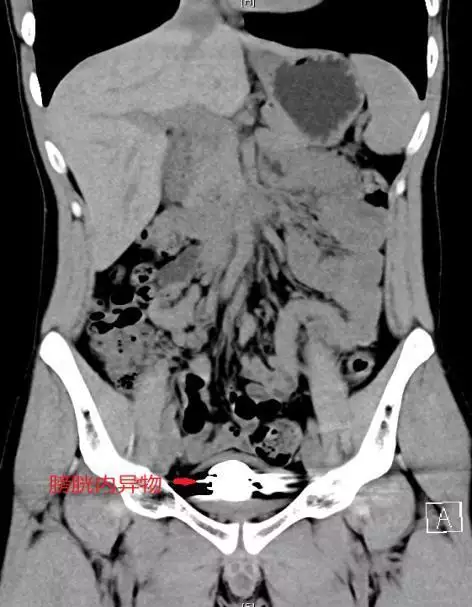

据了解,22岁的简轩(化名)因尿频、尿急、尿痛持续一年,近期症状加重才前往长沙中心医院泌尿外科就医,经影像学检查发现,其膀胱内竟积聚大量直径约5毫米的金属圆珠,排列紧密且表面已形成钙化外壳。该院泌尿外科一区主任傅发军及其团队结合病史及临床经验判断异物为数十颗磁性钢珠,如不及时取出,长期滞留可能导致尿路梗阻、感染甚至组织损伤。

由于异物数量多、磁性强且表面光滑,传统开放手术创伤较大,团队研究后决定采用“经尿道膀胱镜钬激光碎石取异物术”。手术需克服三大难点:磁珠相互吸附难以分离、表面光滑不易抓取、膀胱壁脆弱易损伤。医疗团队通过精准影像定位和精细操作,历时2小时成功取出全部异物,共计50颗磁性钢珠。术后患者症状立即缓解,恢复顺利。